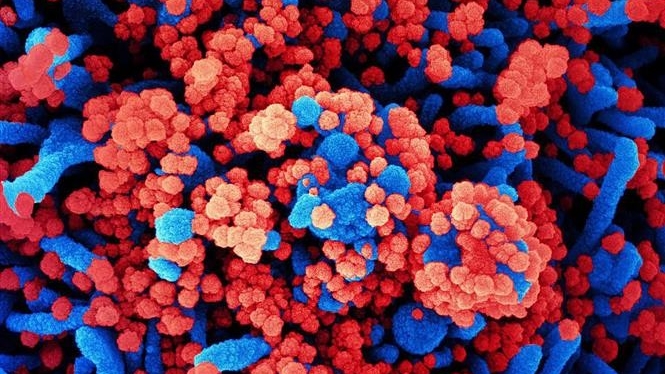

Trên phim chụp X-quang của bệnh nhi. (Ảnh:BVCC)

Tại Bệnh viện Nhi Trung ương, khi tiến hành cho bệnh nhi chụp X-quang và cắt vi tính lồng ngực, các bác sĩ phát hiện dị vật hình kim khâu nằm tại vị trí mặt trước xương bả vai. Cháu C được chỉ định phẫu thuật để lấy vị vật ra khỏi cơ thể.

Trong trường hợp của cháu C, dị vật được các bác sĩ xác định chính xác nhờ phim chụp cắt lớp 128 dãy có dựng hình kết hợp phẫu thuật nội soi vào khoang dưới cân nông giúp giảm sang chấn, tổn thương tổ chức và thẩm mỹ sau mổ.